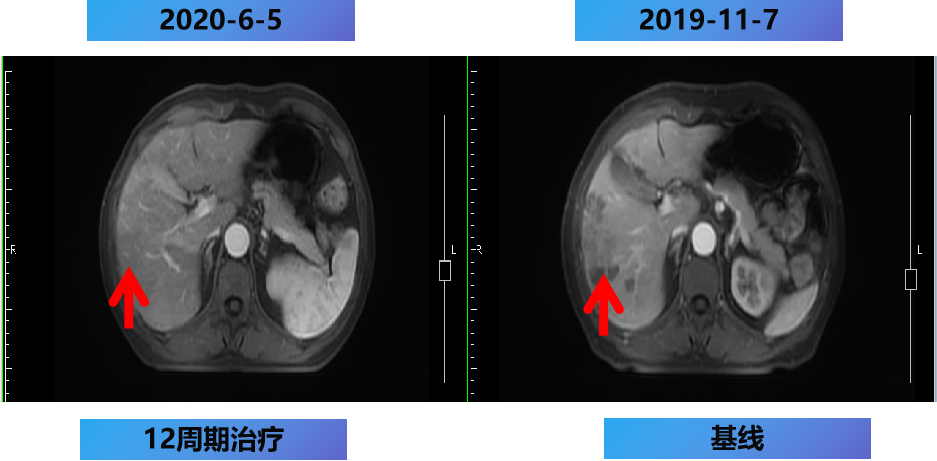

【治疗方案疗效评估】

MDT意见:肝转移灶可切除,肺转移灶缩小。

治疗目标:NED。

治疗策略:原发灶切除和肝转移灶切除,肺转移灶择期手术。

12周期化疗+手术+肝转移灶切除及消融。

2020-7-5 复查腹部MRI示:乙状结肠癌伴肝转移治疗后改变,对比2020-6-18 MRI,肝内治疗灶凝固坏死显著,肝内未见明显癌灶征象,部分周边反应性改变可能,建议3个月后随诊复查。